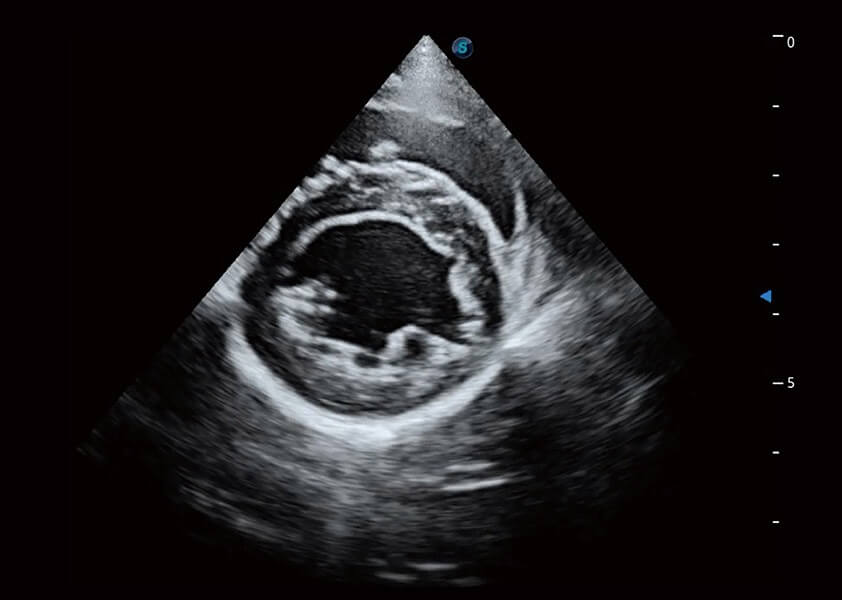

ProPet 60 作为一款高端台式动物超声设备,为动物医生的日常诊断提供了一系列贴合动物临床需求、解决临床实际问题的高级成像功能。凭借全系列高清探头,满足医生对腹部、心脏、生殖、浅表、肌骨等成像的所有需求,切实帮助您提升检查效率,提高诊断信心。

兽用彩色多普勒超声诊断系统